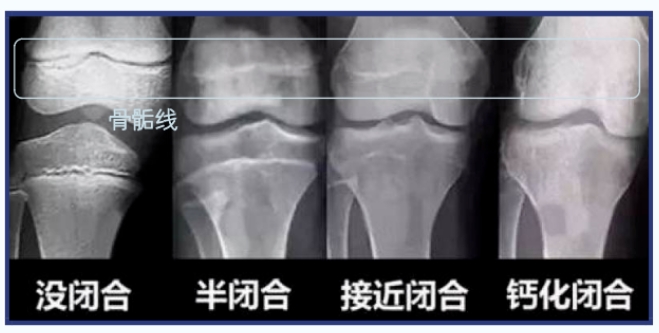

想让孩子长高吗?快带TA来参加这场义诊活动吧,免费测骨龄